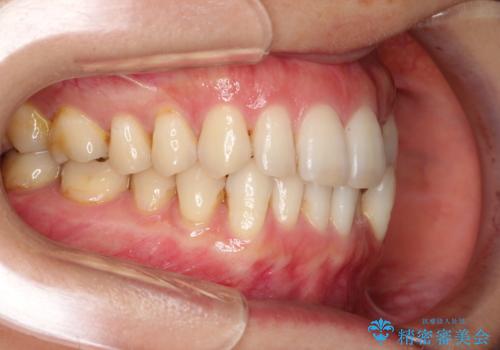

八重歯のインビザライン矯正治療

- 下顎の八重歯と、上下のクロスバイトを気にして来院された患者様です。

インビザラインを用い、下顎全体の後方移動、IPR(歯と歯の間を削る)と歯列全体を拡大させることで、歯並びを整えていくこととしました。